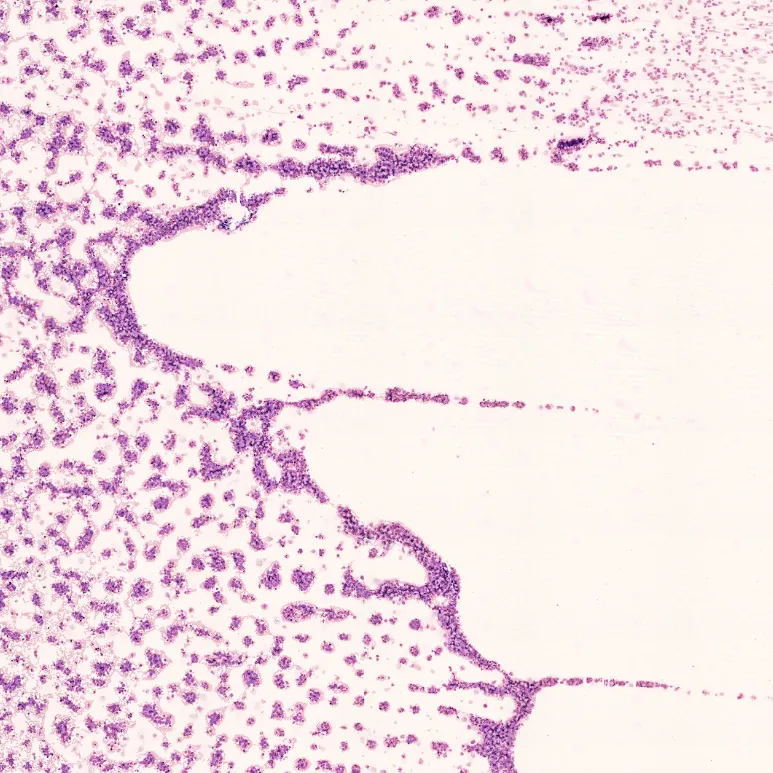

A Full-Field Imaging Perspective

Revolutionary digital imaging captures large scan areas at 100X magnification to give lab professionals a view of all regions of interest, including the feathered edge.